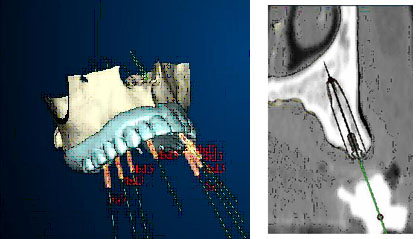

Il paziente esegue una TAC e i dati, tramite un cd, vengono trasferiti nel computer, che ricostruisce con estrema precisione il mascellare e la protesi da realizzare.

Nella fase di pianificazione gli impianti vengono posizionati al computer tenendo conto dell' osso disponibile e, prerogativa esclusiva di questa procedura, del disegno della futura protesi. Il computer realizza quindi la guida che verrà utilizzata dal laboratorio specializzato per realizzare la protesi. La stessa guida permetterà al dentista di posizionare gli impianti con assoluta precisione, senza dover incidere la gengiva, ma praticando esclusivamente dei piccoli fori. Al termine dell' intervento il dentista può applicare la protesi precostruita.